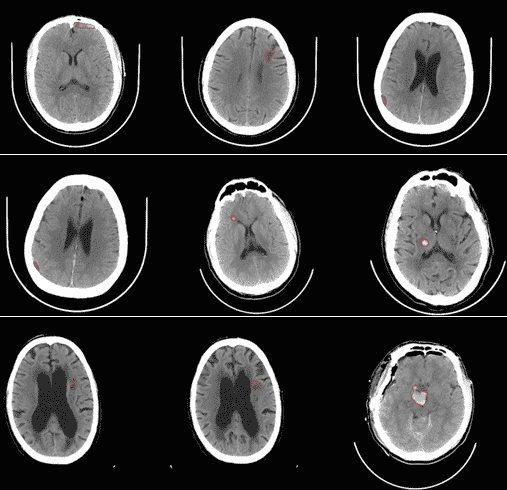

Founded in 2016, San Francisco-based startup Viz has taken in $9.55 million in funding so far from investors that include Yahoo! founder Jerry Yang to aid physicians in identifying anomalies in brain scans using machine learning. It looks like artificial intelligence is already being used to find problems with the primary source of all human intelligence, and the main use case here is the early identification of strokes. According to the American Stroke Association, strokes are the fourth leading cause of death in the U.S. and one of the reasons they are so deadly is because they are so difficult to diagnose. Check out how subtle some of the signs are:

There aren’t that many highly skilled neurologists around when you do need to make a quick diagnosis so AI is stepping in to address this gap. As we mentioned before, an AI algorithm can also digest an entire electronic health record in seconds while a neurologist wouldn’t have the time to. And as Viz tells us, “when the brain is injured, every second matters”.